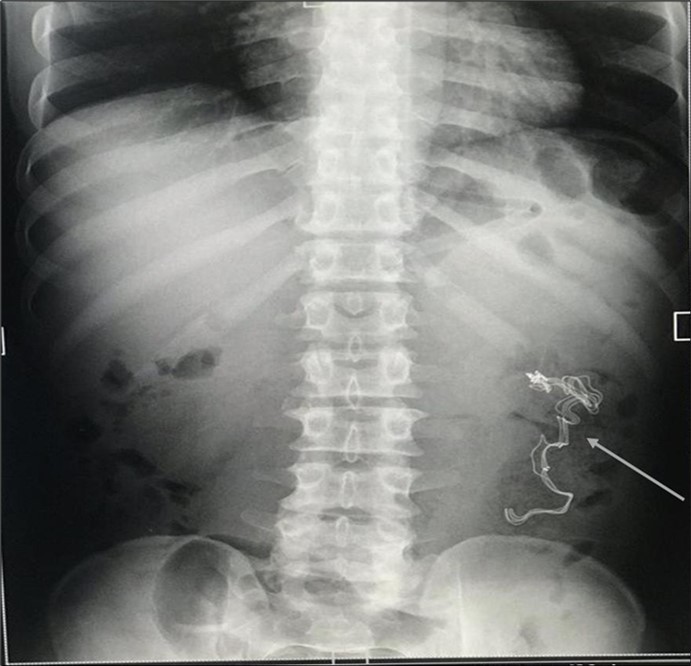

An impression of an intestinal obstruction due to postoperative adhesions was made. An abdominal X-ray done showed no obvious signs of bowel dilatation but an ill-defined opacification in the area of the left lumbar region (Figure 1). An ultrasonography done showed an echogenic mass in the left iliac region measuring about 4.1cm in diameter. There was no flow on colour doppler interrogation (Figure 2). At this point a diagnosis of foreign body was queried. The patient was counselled and prepared for exploratory laparotomy.

Figure 1.Erect abdominal X-Ray showing an ill-defined opacification in the left lumbar region (arrowed).